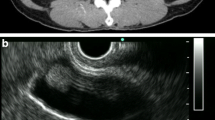

Examinations including whole body computed tomography (CT) before each surgery demonstrated no evidence of distant metastasis. A surveillance follow-up CT scan revealed a gallbladder lesion. No symptoms suggested cholecystitis, and the only biochemical abnormality was a slight elevation in levels of aspartate transaminase and alanine transaminase. Ultrasonography (US) showed a mass at the gallbladder fundus. Its surface was smooth, and the inner echo was slightly high and homogenous (Fig. 1).

A contrast-enhanced CT scan showed a 12-mm polypoid mass with high attenuation, enlarged from 4 mm 2 years ago (Fig. 2a, b). It had significantly high intensity in the arterial phase. On the coronal reconstruction image, attenuation was inhomogeneous in the mass and relatively higher on the wall side (Fig. 2c, d). There was no significant accumulation of contrast agent in any organ other than the gallbladder.

A computed tomography scan shows tumor growth from 4 mm to 12 mm over a span of 2 years (a 2 years prior, b present). A contrast-enhanced computed tomography scan shows high intensity of the tumor during the arterial phase (d yellow arrow) in comparison with plain computed tomography (c yellow arrow)